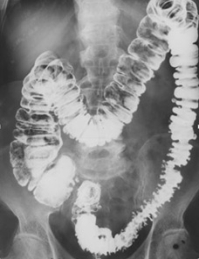

Дивертикулез ободочной кишки.

|